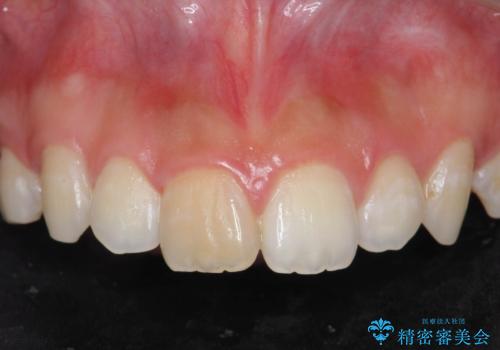

前歯の変色をキレイに セラミッククラウン審美治療

- 前歯の変色が気になる、見た目を改善したい!と審美性の回復を希望され来院されました。

ホワイトニングでは、周囲の歯との色調になじむほどには白くできないため、ジルコニアセラミッククラウンを用いて審美性を回復します。

周囲の歯の色調に調和した審美性の高いセラミッククラウンを製作することができました。